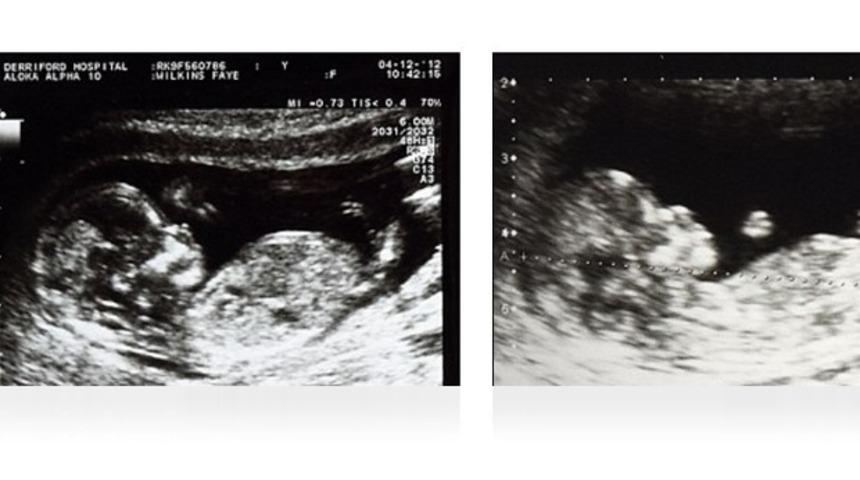

İki çocuğu, iki farklı rahimde taşıdı

Ergenliğe girdiğinde bir türlü regl olmayan Wilkins, bir gün karnında patlama hissi yaşayınca doktora gitmiş. Birçok kez doktora gittikten sonra doğru teşhis koyulan genç anne durumunu ilk öğrendiğinde inanmakta güçlük çekmiş. Patlama hissinin nedeni ise iki vajina olması nedeniyle yumurtalıkları çatlayıp kanama yarattığında dışarı çıkamamış olması.

İki vajinası olması nedeniyle regl olamadığı ortaya çıkan Wilkins'in yapılan bir operasyonla vajinası birleştirilmiş ancak serviks ve rahmi hala 2 tane. Wilkins anne olmak istediğinde ise birçok zorlukla karşılaştı. Genç kadın ilk kızı Molly'i kucağına almadan önce tam 6 kere bebeğini düşürmüş. Molly'ye hamileyken, kızının babası tarafından terk edilen Faye Wilkins, 2 kez daha bebeğini düşürdükten sonra yeni partneri ile George'u doğurmuş.

Çift rahimli olma henüz anne karnında bebek fetüs halindeyken oluşan bir şey. Durum genellikle ergenlik çağında, ultrason ile muayenede ya da regl döneminde ortaya çıkıyor. Çift rahimli insanların aynı anda iki farklı bebeğe hamile kalması mümkün.